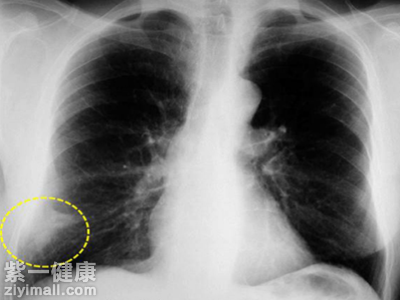

在臨床醫(yī)學上面,現(xiàn)在的CT影像能夠觀察小于2毫米的肺小結(jié)節(jié),從而加大了醫(yī)生診斷的難度。查出肺部小結(jié)節(jié)并不就意味著我們得了肺癌,有很多的良性疾病的表現(xiàn)癥狀也是會出現(xiàn)小結(jié)節(jié)的。根據(jù)有關(guān)報道顯示,患有肺部微小結(jié)節(jié)病的患者有百分之七十三的惡性可能性,主要病癥是肺腺癌。肺結(jié)節(jié)良性有百分之二十七的可能性,可能患有血管瘤、肉芽腫病變或者是結(jié)核瘤等病癥。